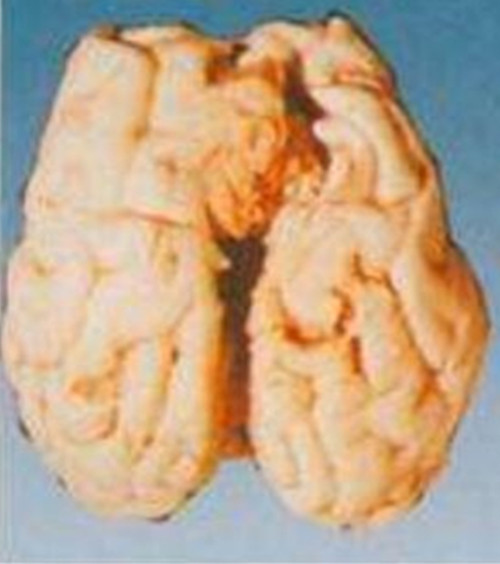

細菌性腦膜炎

細菌性腦膜炎的腦

腦膜炎細菌性腦部